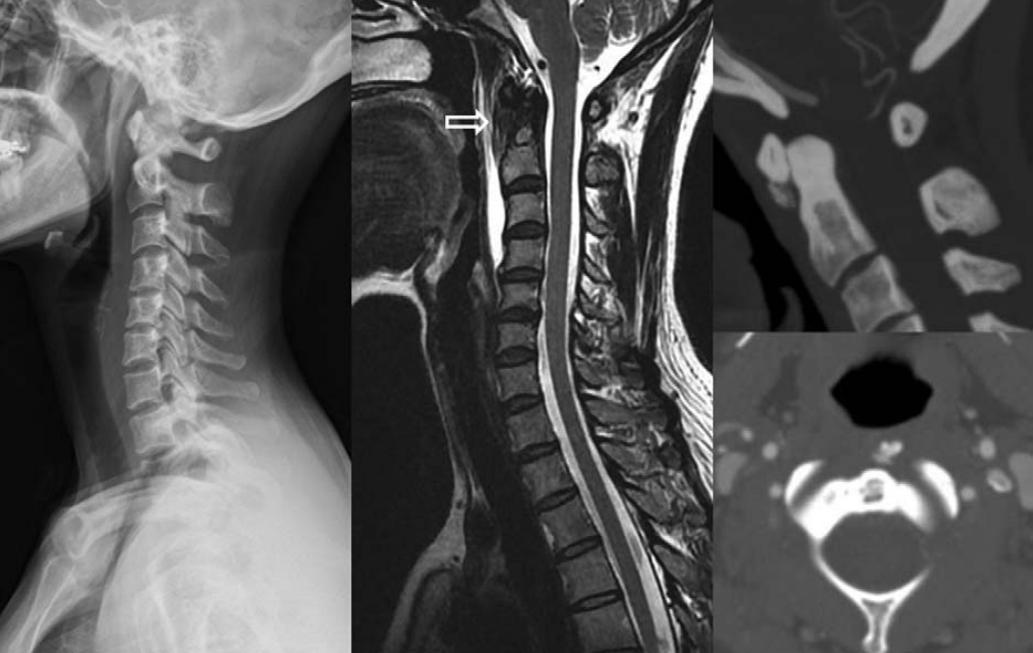

32岁男性,颈肩部疼痛1月,喝水时轻度吞咽困难伴颈椎活动受限,无发热,化验指标正常,经非甾体抗炎药和秋水仙碱治疗后症状改善,4月后复查颈椎侧位片(D,E)钙化消失。(PMID: 25941110)

颈椎侧位片能够显示上颈椎前纵韧带和颈长肌组成的软组织影增宽,密度增高,正常时宽度为3-4mm,急性炎性水肿时可增宽到1cm以上,并可显示椎前软组织内的钙化影,一般位于C1-2水平 。此外,还可见颈肌痉挛引起的颈椎前凸消失。颈椎侧位平片所见的发育性寰椎前弓的下方附属小骨片、寰椎前弓的撕脱骨折以及茎突舌骨肌韧带的钙化极易与本病所见的钙化混淆。

CT的高分辨率能够明确肌腱内的钙化,能够明确是钙化而不是其他骨骼来源的高密度影。 钙化一般位于寰椎前弓的下方和枢椎齿状突的前方,少部分可位于下颈椎前侧 。CT有助于明确椎体前积液的存在和排除其他病理表现,如骨折或脓肿。MRI对诊断不是必须,但有时可帮助确定软组织异常,排除咽后脓肿,脊椎炎或肿瘤。 MRI检查T2加权在椎前可见局限性的裂隙样区域,大多位于C1-4水平,呈高信号改变,这反应是由于炎症引起的积液 。T2加权、脂肪抑制序列和T1加权对鉴别积液和脂肪组织、含脂肪的骨髓以及咽后感染、脊椎炎有重要作用。MRI检查在钙化检查方面存在不足,T2加权呈低信号。